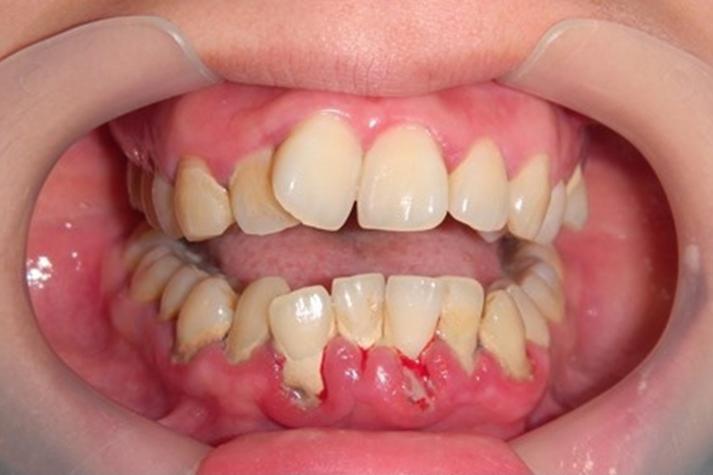

很多人刷牙时看到牙刷上有一点血,并不会太在意,甚至觉得是牙刷太硬造成的。然而如果牙龈出血频繁出现,尤其是在轻微触碰或者吃东西时就出血,这种情况往往提示牙龈组织已经存在炎症。牙龈炎和牙周炎是导致牙龈出血最常见的原因。

当口腔卫生状况不理想时,牙菌斑会逐渐堆积在牙齿和牙龈边缘。菌斑中的细菌会刺激牙龈组织,导致局部炎症反应。炎症状态下,牙龈血管会变得更加脆弱,因此在刷牙或咀嚼食物时就容易出血。然而问题并不仅仅局限在口腔。

牙龈长期炎症可能让细菌和炎症因子进入血液循环,从而影响全身系统。一些研究已经发现,牙周炎患者发生心血管疾病的风险明显增加。例如某些大型流行病学研究显示,牙周炎患者出现冠心病的概率比牙龈健康人群高出约20%到30%。此外,牙龈出血还可能与血糖状态有关。